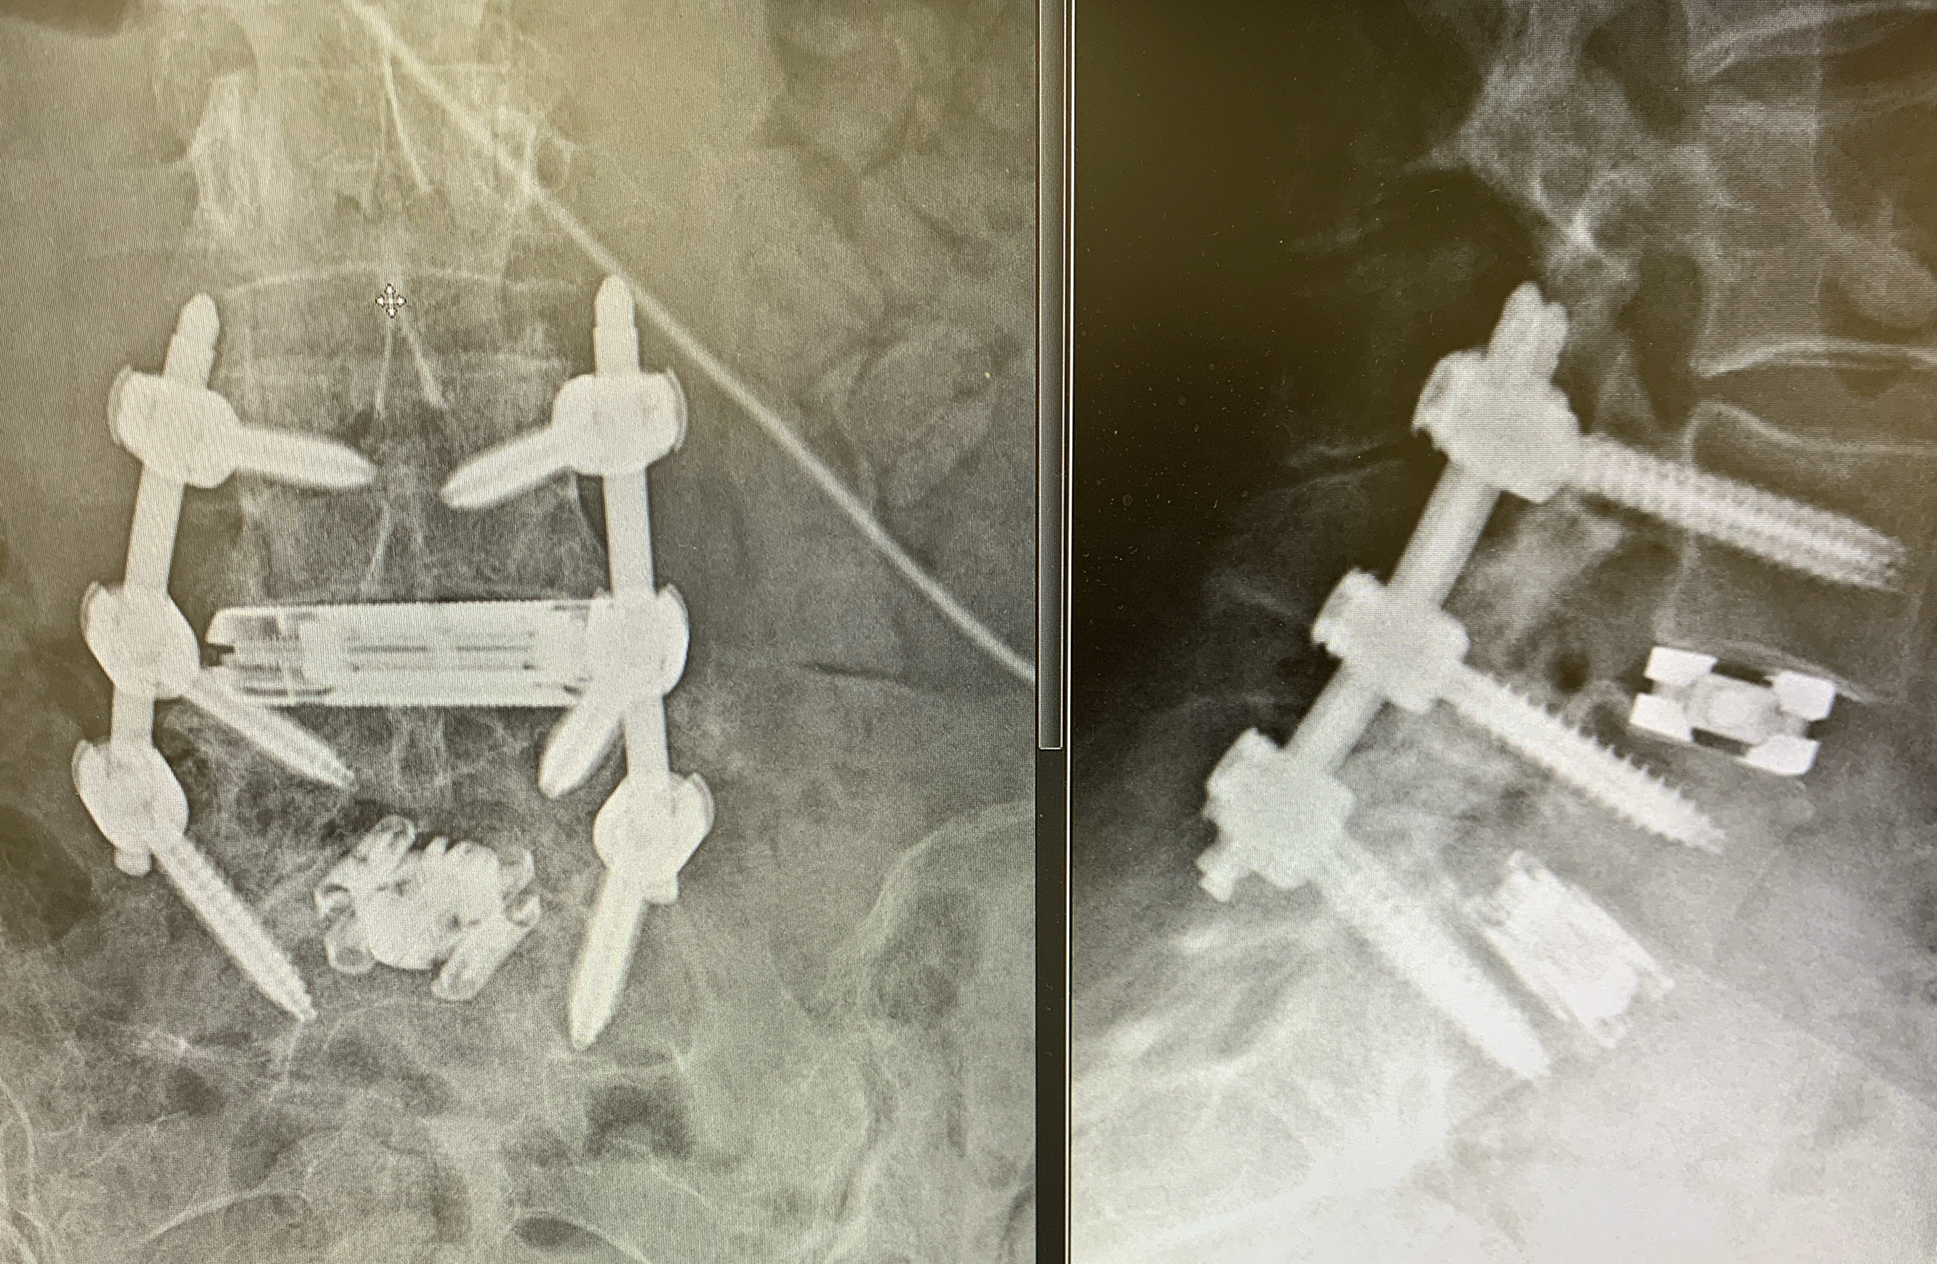

Unique LLIF Interbody Solution for Small Portal Access

The dualX® LLIF solution is a comprehensive expandable interbody cage system for small portal access. dualX® LLIF is designed to minimize neural retraction while achieving maximum implant geometry.

The procedure is performed completely through an 18mm opening, reducing the potential psoas retraction up to 50%.

Vertical expansion assists in direct and indirect decompression

Heights 7mm* expanding to 17mm*

Width 13mm expanding to 22mm

Final Length 40 to 60mm

0°, 7°, 12° and 18° Lordosis*